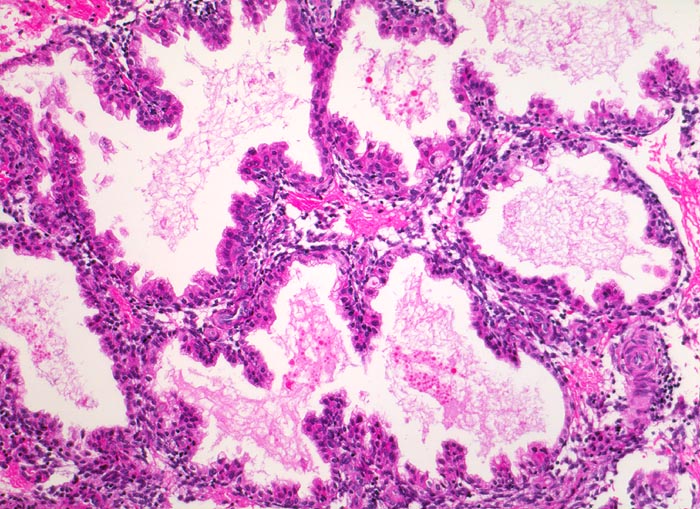

Abortkurettage: Schwangerschaftsendometrium

Das Schwangerschaftsendometrium besteht aus stark proliferierten hypersekretorischen ausgeweiteten Drüsen. Das Drüsenepithel bildet papilläre und pseudopapilläre in die Drüsenlumina hineinragende Proliferate. Die Zellkerne des Drüsenepithels sind hyperchromatisch und polymorph (sogenanntes Arias Stella Phänomen).

Missed abortion in der 11. Schwangerschaftswoche, sonographisch entsprechend der 9. Schwangerschaftswoche.

200